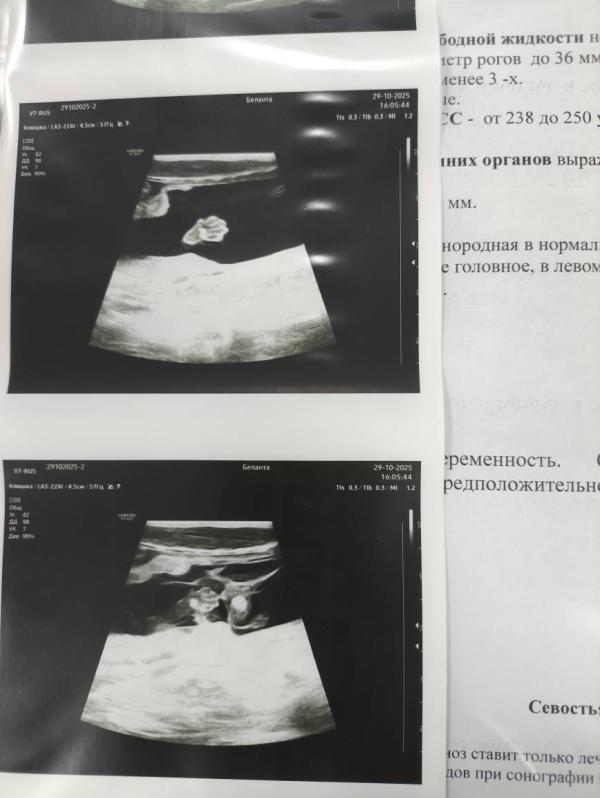

Когда в твоём пузике поселились три пузожителя 🤗

Они родятся в ноябре, к новому году подрасти не успеют, нужно будет немного подождать